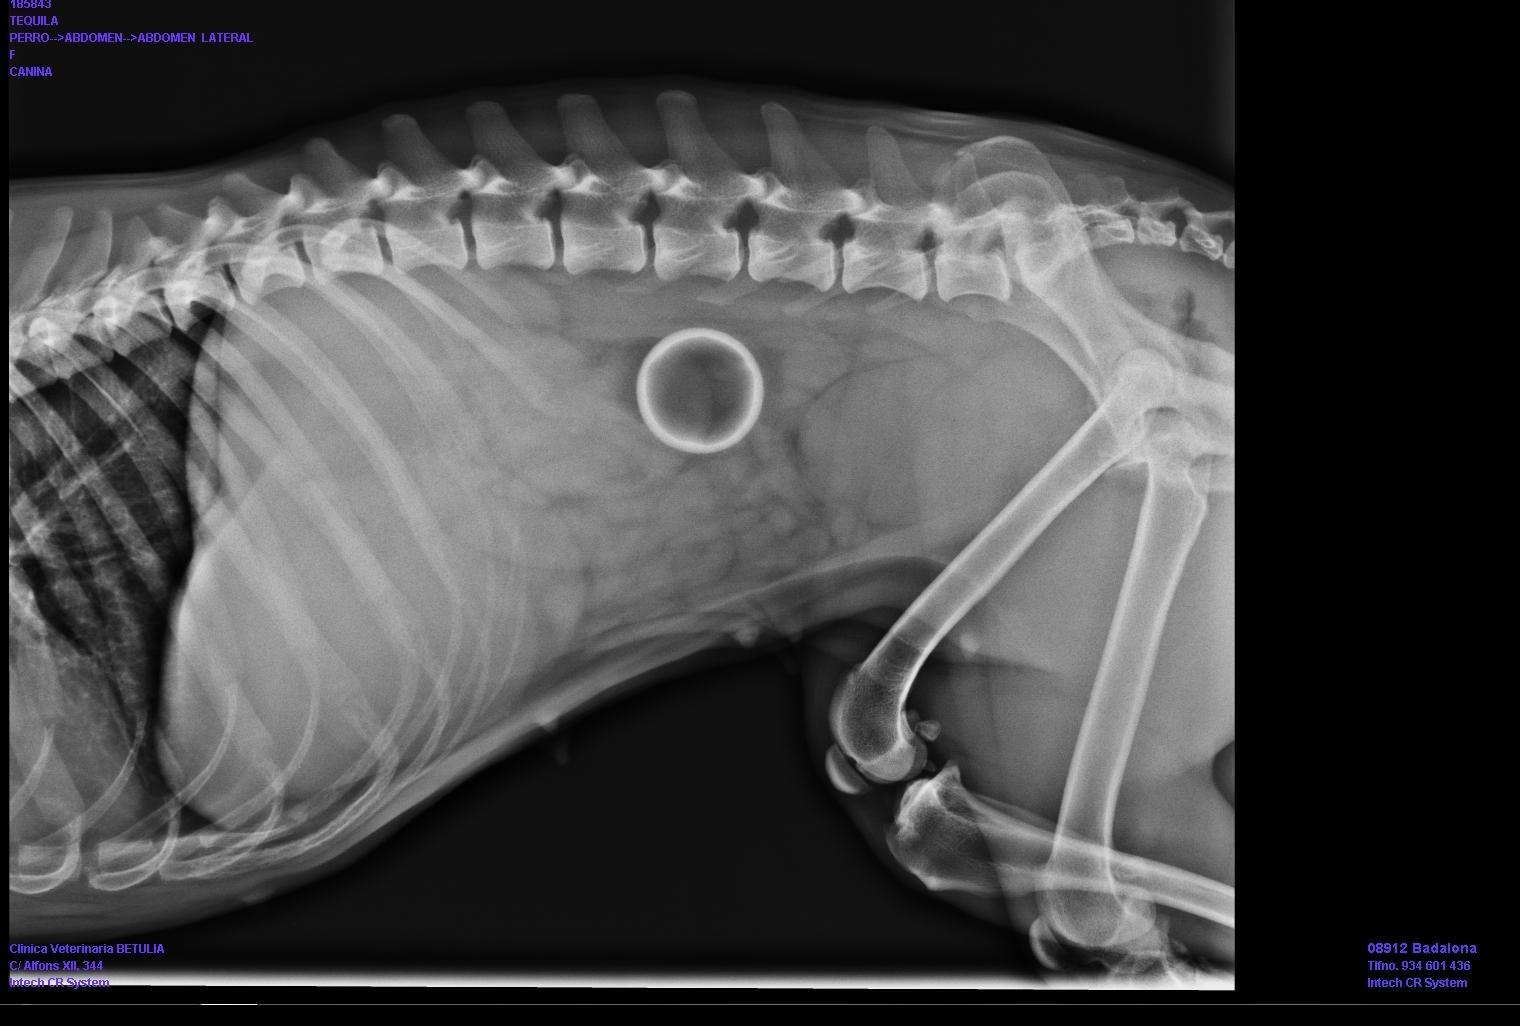

Para detectar uma obstrução intestinal em cachorros o veterinário pode fazer uma radiografia do abdome. Nesta se pode verificar a distensão dos intestinos e uma grande quantidade de gases. O tratamento, logicamente, deve aliviar esta obstrução. O tratamento de eleição, em geral, vai passar por cirurgia e somente o veterinário pode determinar, uma vez examinadas as características da obstrução, e se é possível aliviar a mesma administrando algum fármaco.